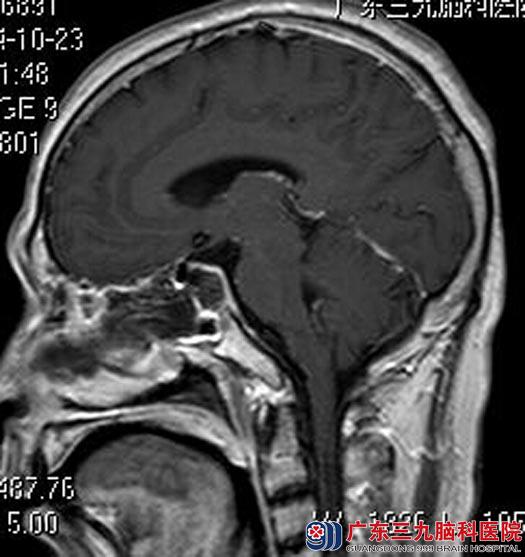

就诊广东三九脑科医院垂体瘤诊疗中心,进一步MR检查发现:鞍区一类哑铃状占位性病变,大小约1.6cm×1.8cm×3.1cm,考虑垂体瘤并卒中可能性大。

考虑到田先生的病情发展时间短、进展快,完善相关检查后,立即由鲁明主任主刀,在全麻下行经鼻蝶入路垂体瘤切除术,术中再次导航定位,显微镜下切除肿瘤组织,垂体保护完好,未见明显脑脊液漏。术后田先生的眼睛基本恢复正常。术后病理结果:垂体腺瘤伴出血。